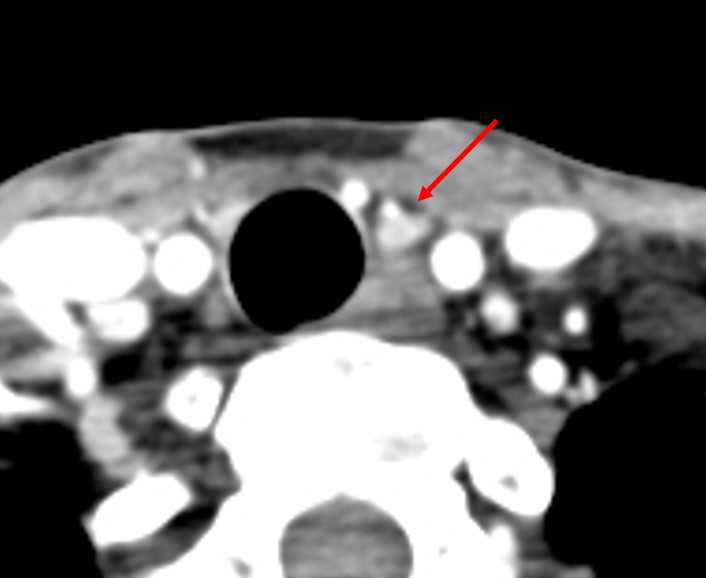

[353,] 42/F,검강검진상 발견된 갑상선 병변

Modality

US,CT,

Sae Rom Chung

,2025-10-25

진단은?

[Diagnosis]

Diffuse sclerosing subtype of PTC